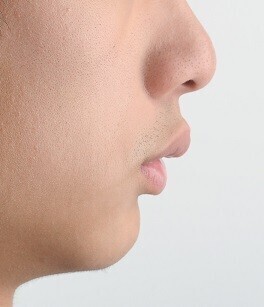

2. 돌출입교정

8. 비수술무턱교정